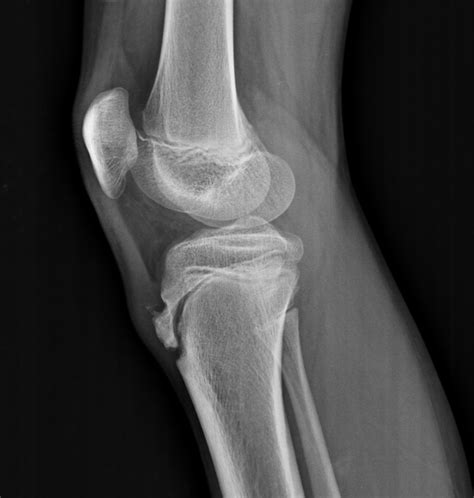

Osgood-Schlatter disease | The Third Eye - Radiology site